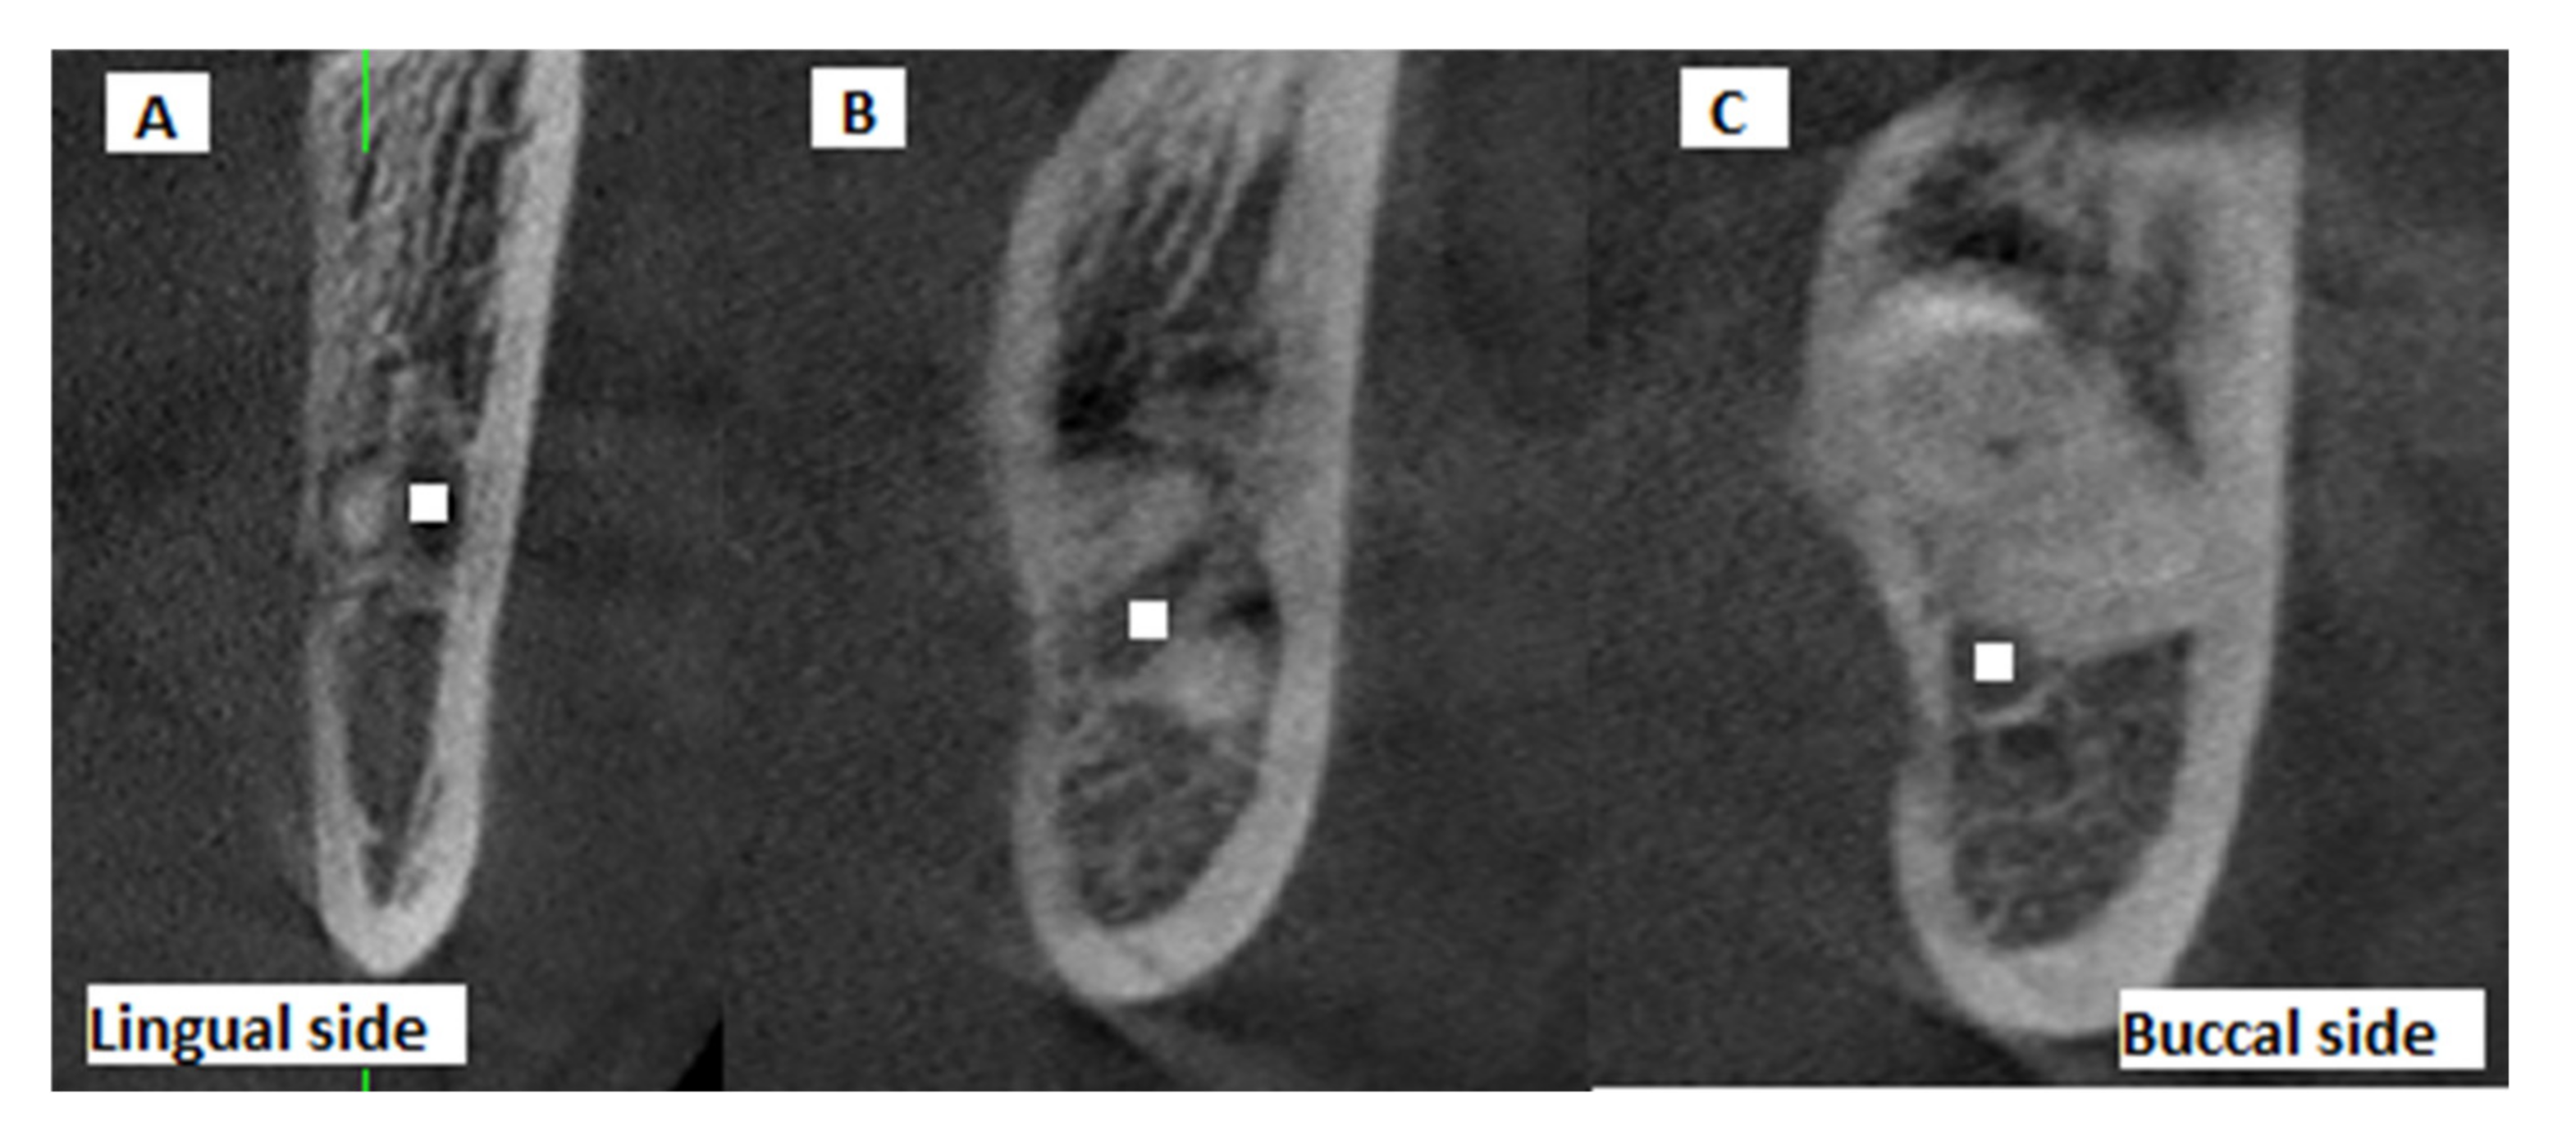

Moreover, the position of the MC relative to the root apex of the IMTM (lingual, inter-radicular or buccal position) was determined on the CBCT scans and recorded (Figure 3). The presence/absence of contact between the MC and the IMTM root was also evaluated on coronal, axial, and cross-sectional CBCT views and recorded.

Figure 3.

Cross-sectional CBCT views showing the buccolingual position of the IMTM apex relative to the MC: (A) buccal, (B) inter-radicular, (C) lingual (white squares: center of mandibular canal).